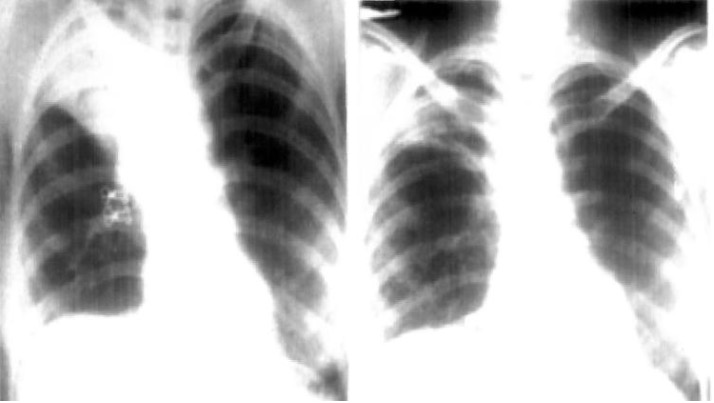

Ao refazer os exames, o teste para a doença deu negativo, e foi descoberta uma lesão em um lobo pulmonar superior da paciente, e encontrada uma "estrutura semelhante a uma bolsa invertida 'parada' no brônquio”. Após cirurgia os médicos perceberam que se tratava de uma camisinha.